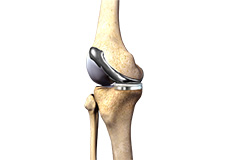

Total Knee Replacement

Total knee replacement, also called total knee arthroplasty, is a surgical procedure in which the worn out or damaged surfaces of the knee joint is removed and replaced with an artificial prosthesis.

Knee Implants

Knee implants are artificial devices that form the essential parts of the knee during a knee replacement surgery. The knee implants vary by size, shape, and material. Implants are made of biocompatible materials that are accepted by the body without producing any rejection response. Implants can be made of metal alloys, ceramic or plastic, and can be joined to the bone.